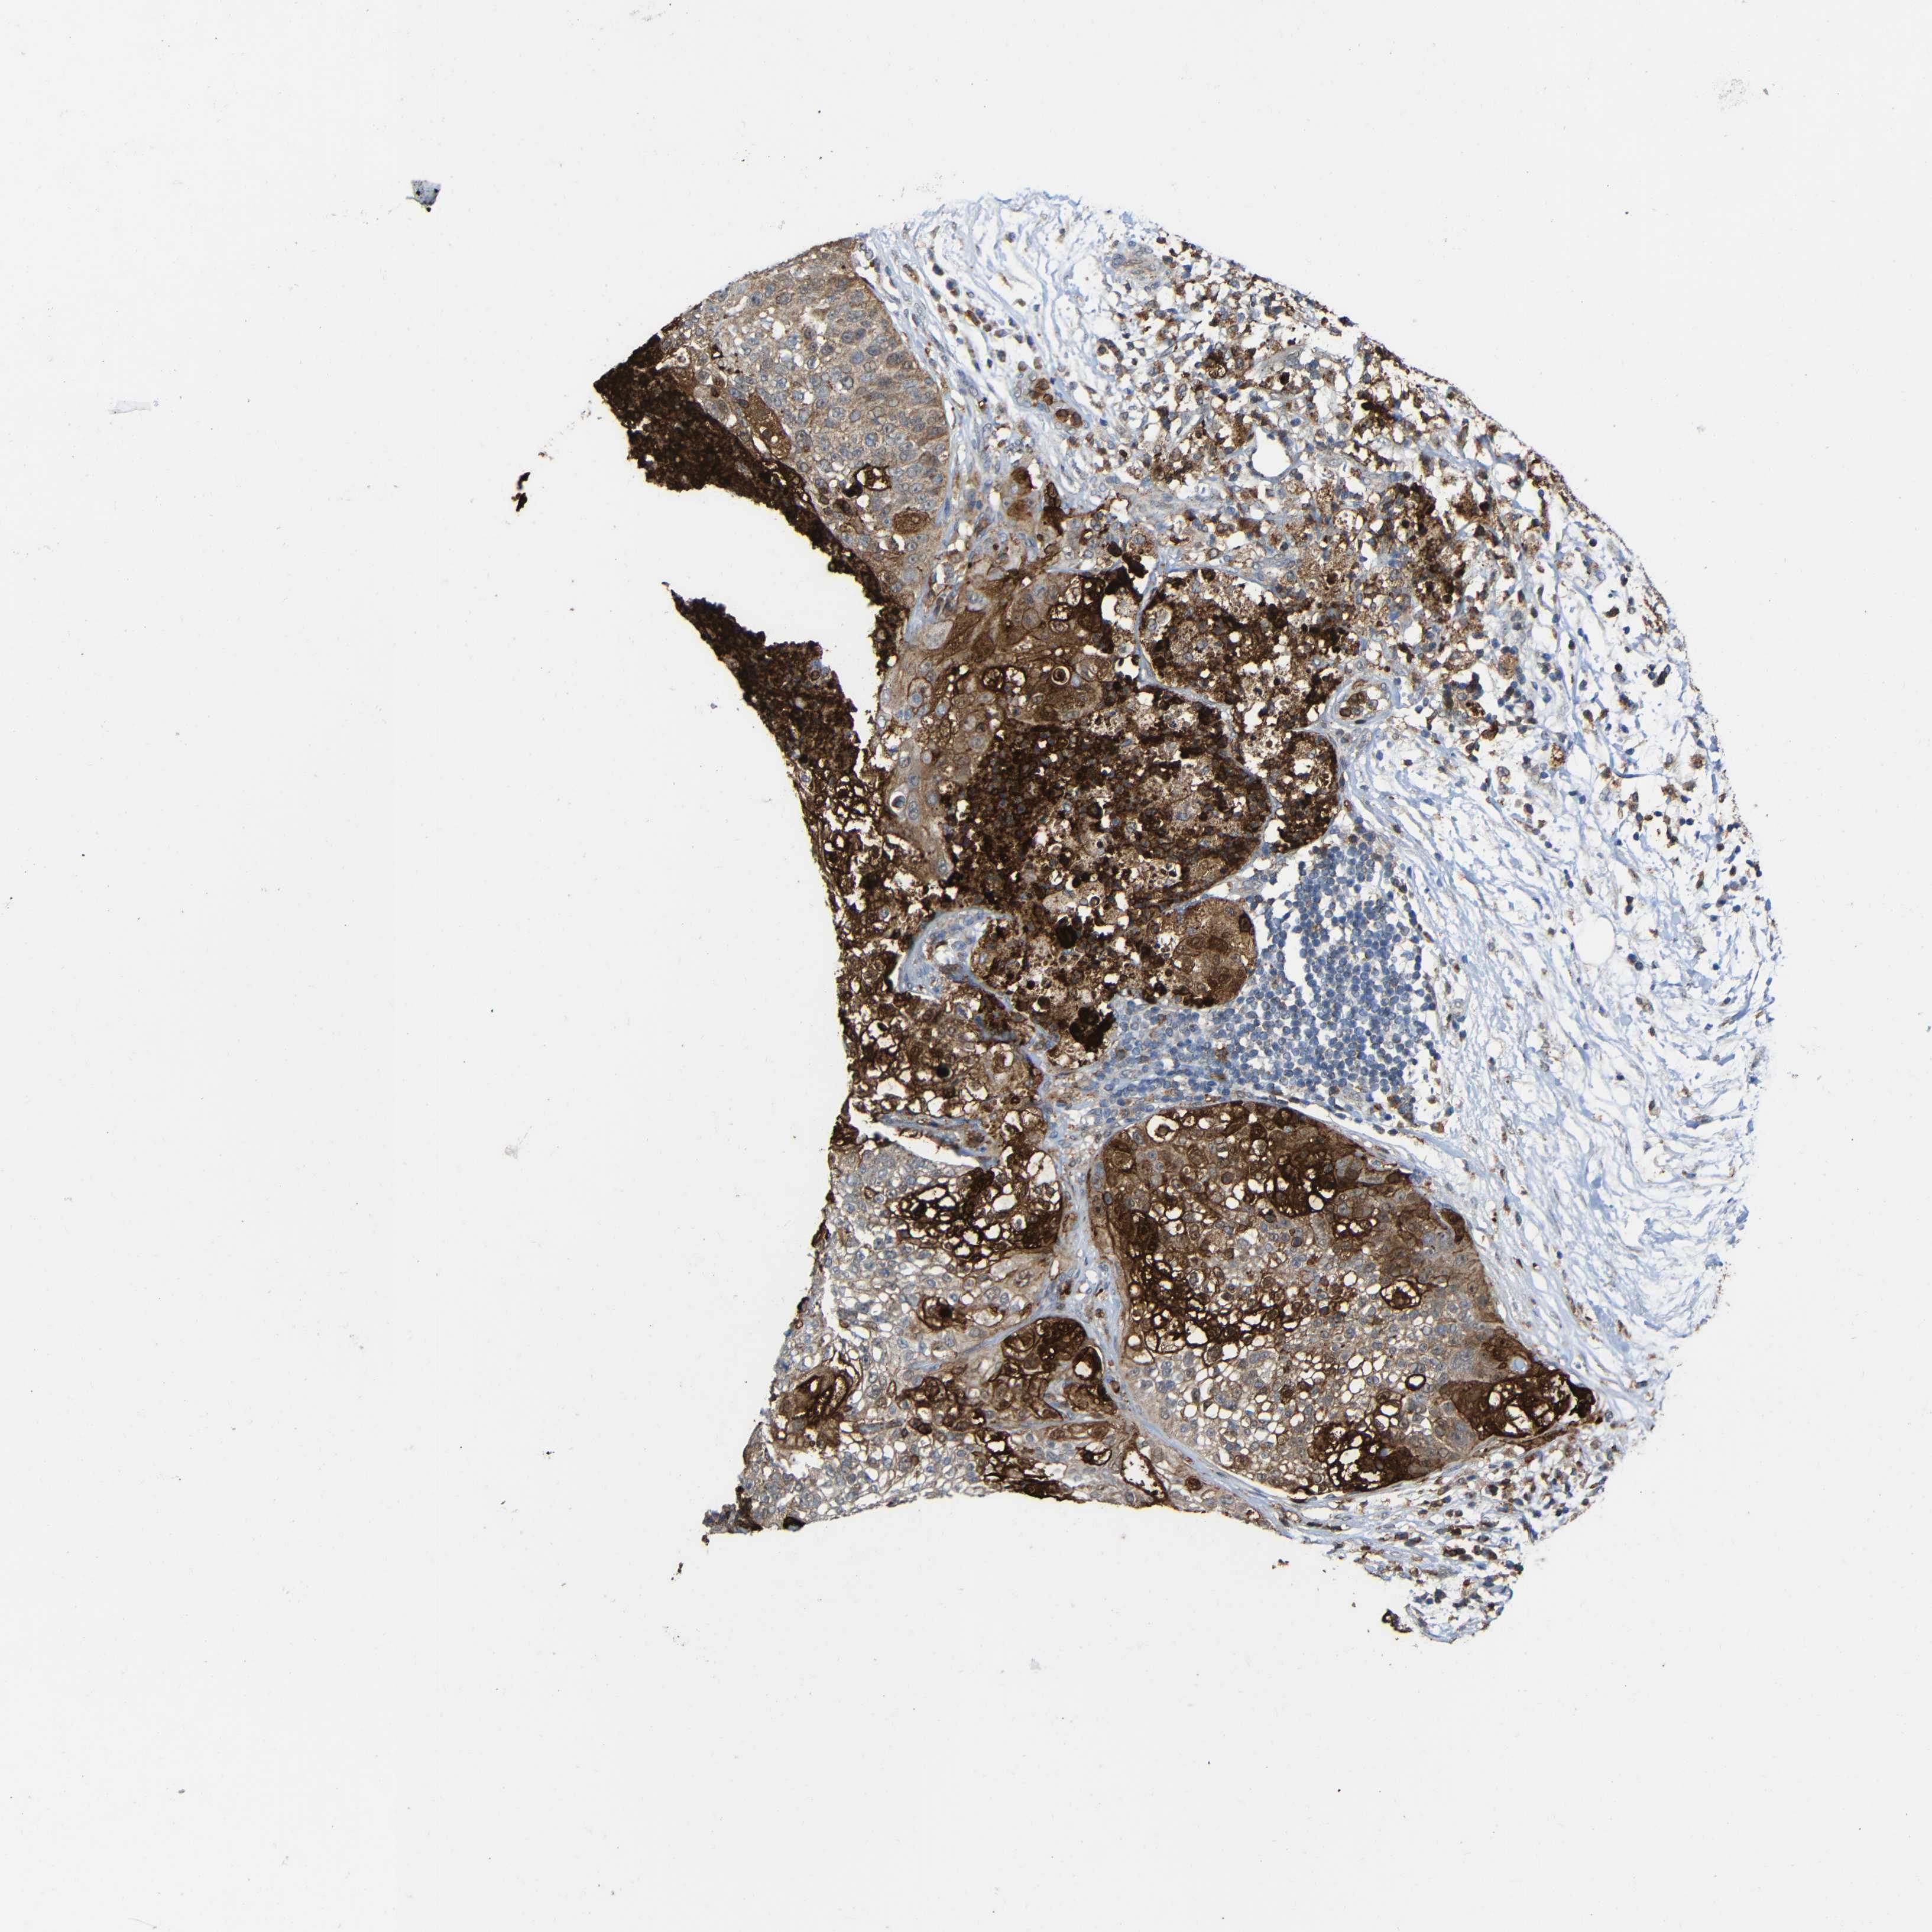

LUNG ADENOCARCINOMA (VALIDATION) - Interactive survival scatter ploti

C1GALT1 is not prognostic in Lung Adenocarcinoma (validation)

: 40.57

Average pTPM 48.5

Number of samples 105